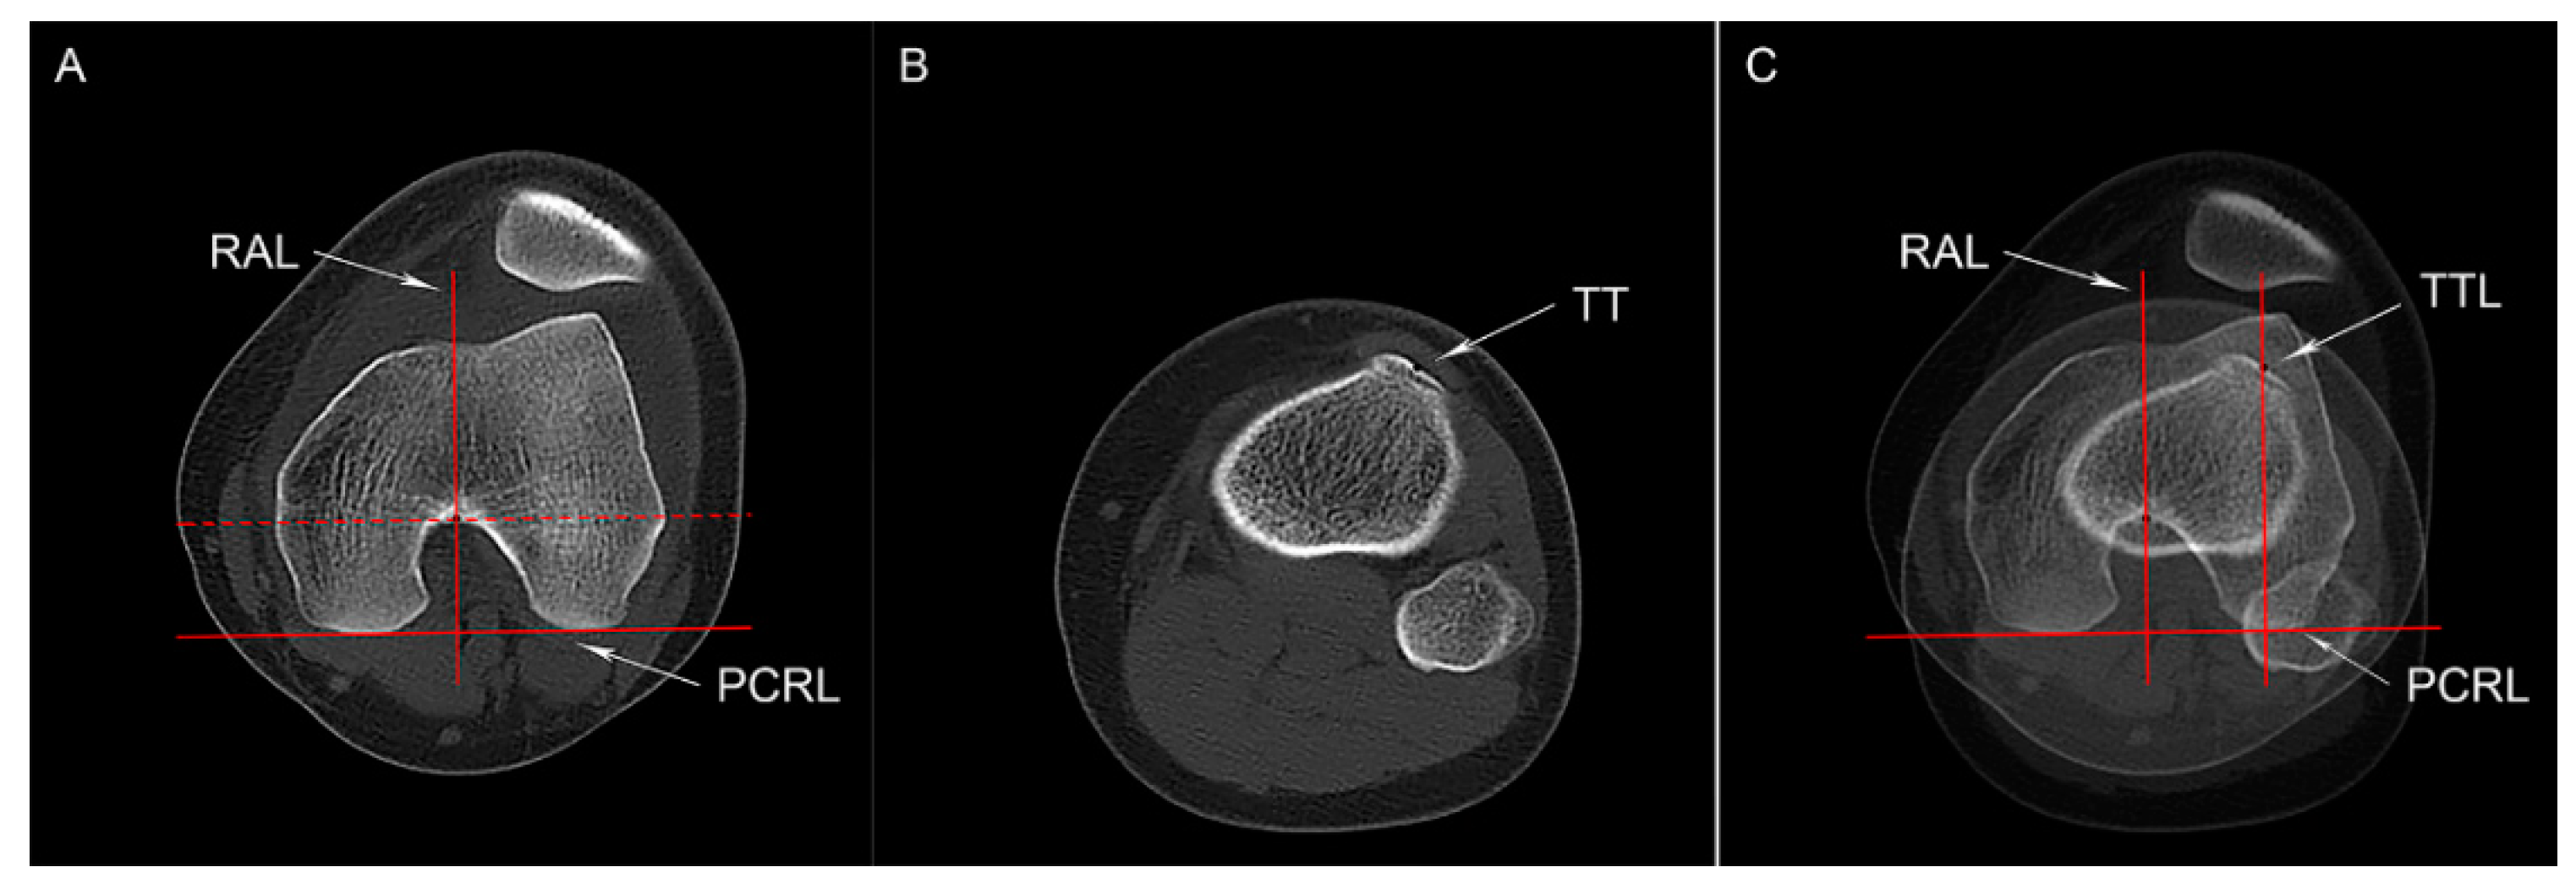

2.4.3. TT-RA Distance

2.4.4. Knee Joint Rotation and Patellar Height